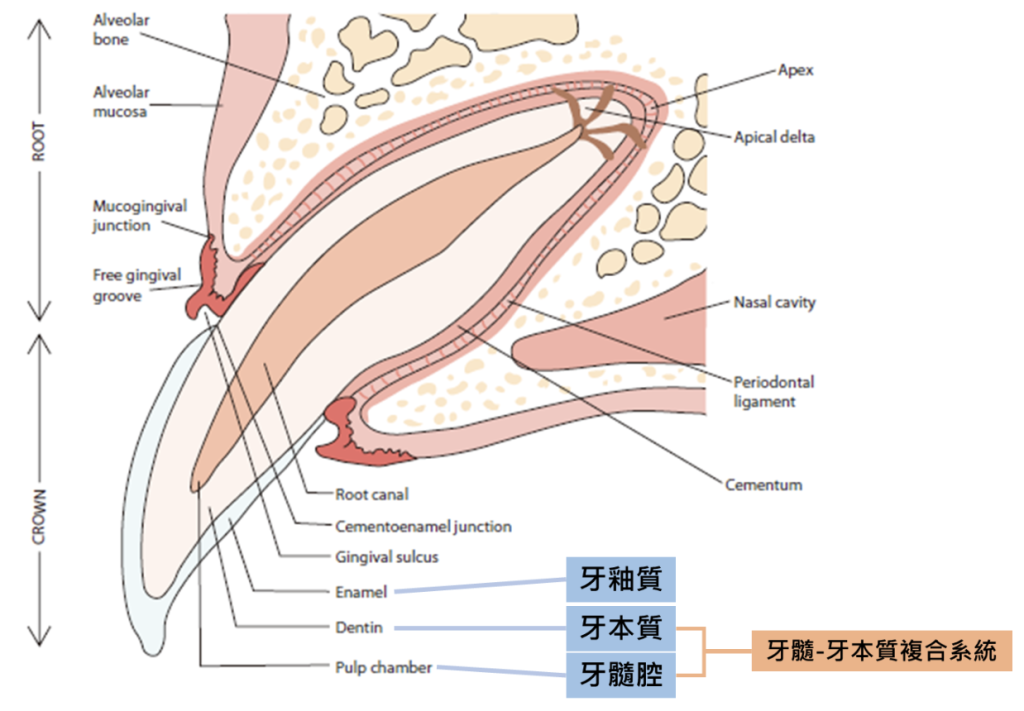

「根管治療」一般俗稱「抽神經」,但可不是真的把神經從牙齒裡面抽出來唷!牙齒在一般的狀況下屬於封閉式的結構,由外而內組成為:「牙釉質、牙本質、牙髓腔」,而「牙本質、牙髓腔」這兩個部分又被稱為「牙髓-牙本質複合系統」,內含有小血管、神經以及淋巴等組織。

當因牙齒斷裂、磨損導致牙髓暴露,進而使牙髓腔出現感染、壞死的情形時,需要即時清除這些感染源及壞死組織,以保留最多的健康齒質,故抽「神經」的意思,就是清除「牙髓-牙本質複合系統」的發炎部分,來進行「根管治療」。

圖片來源:https://wsava.org/wp-content/uploads/2020/01/Dental-Guidleines-for-endorsement_0.pdf